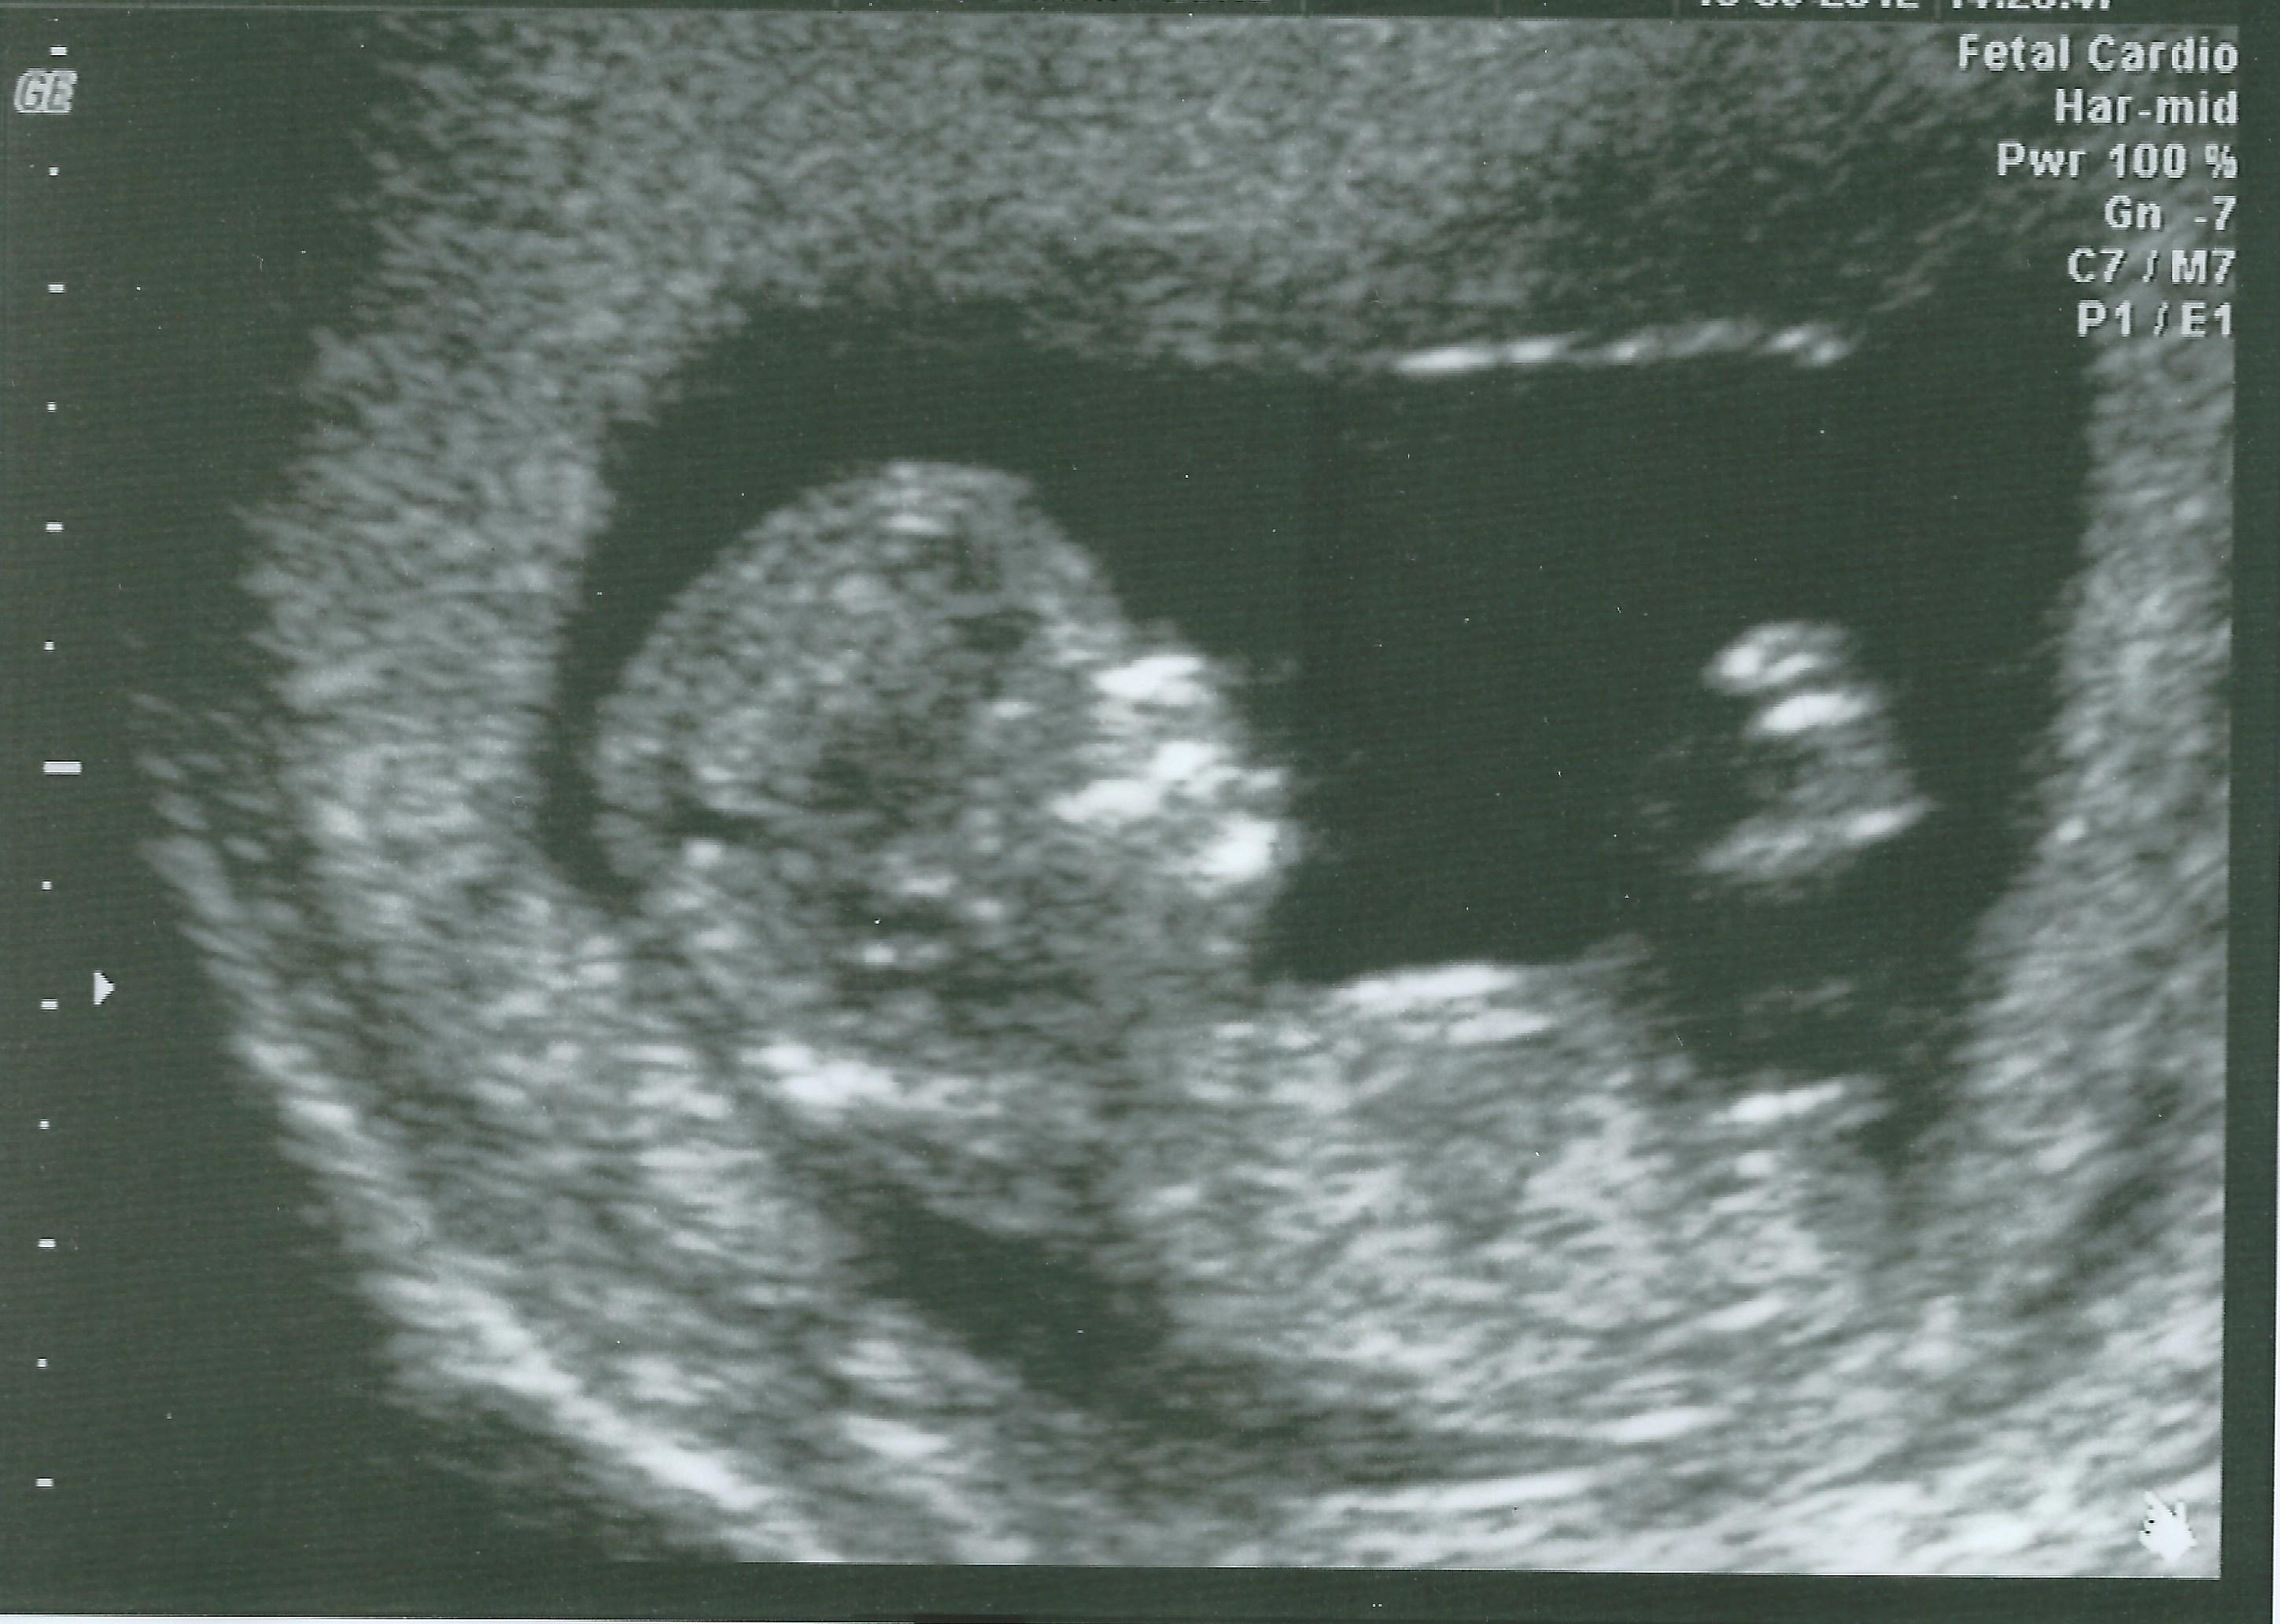

total boy! that angle if thats the nub is super high!

Girl. I think that the angle is deceiving because the baby is so curled up. The nub is nice and long - girl!

With the baby being so early and curled up like that it could go either way. Have any more pics?